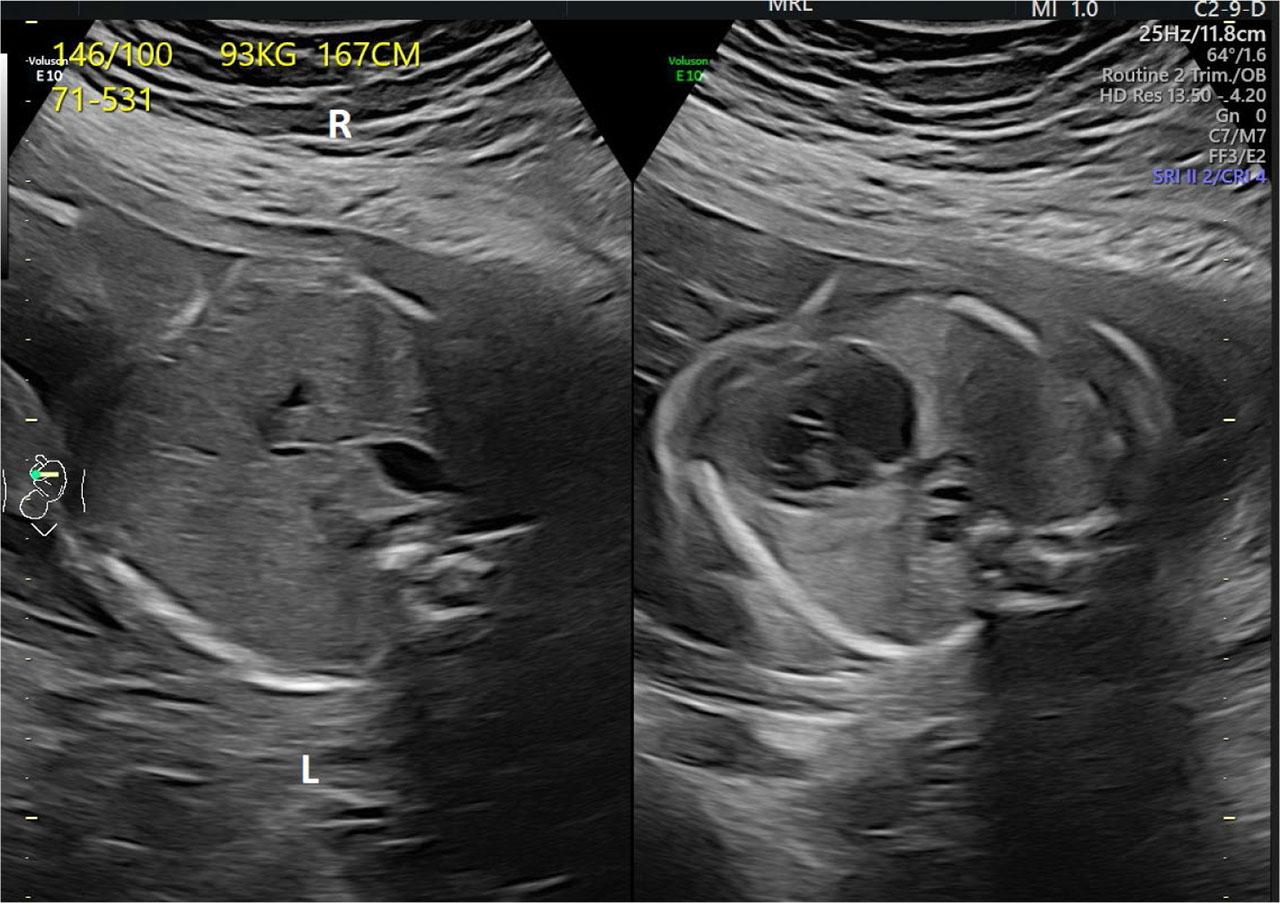

Fig. 1.